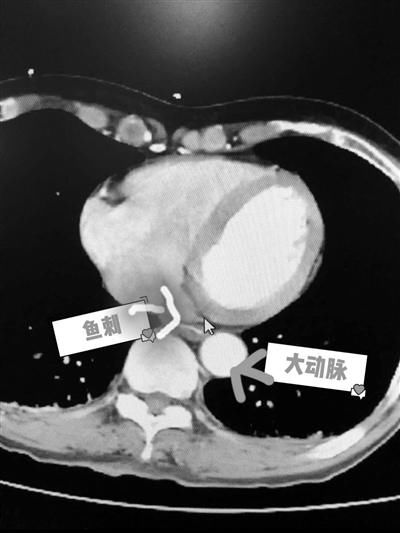

鱼刺卡在食道危及大动脉 图片由浙二陈医师提供

医生看片子发现,大姐吞下的是一块刀片形鱼刺,虽然薄,但边缘锋利,就像刀片一样扎在食道里面,而且边上就是最大的血管胸主动脉,万一扎到主动脉,就会引发大出血,后果不堪设想。